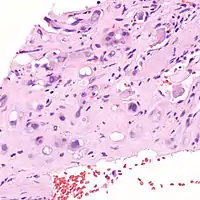

Micrograph of an epithelioid hemangioendothelioma of the liver.